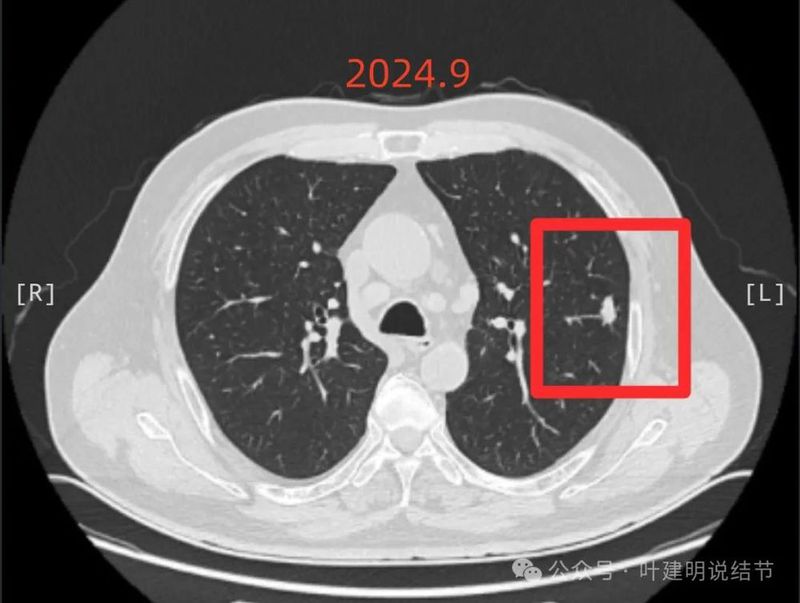

2024年9月24日 病人感冒,咳嗽,入住当地三甲医院,依然按炎症处理,此时左肺上叶段结节14*9mm,右肺上叶5*4mm结节, 引起重视,CT及影像见附件1 ;

2024年9月再增大进展,见血管进入明显,靠血管这侧的边缘较为毛糙。

局部放大病灶表面不平,血管进入,进入的血管有异常增粗,没有见到明显卫星病灶。